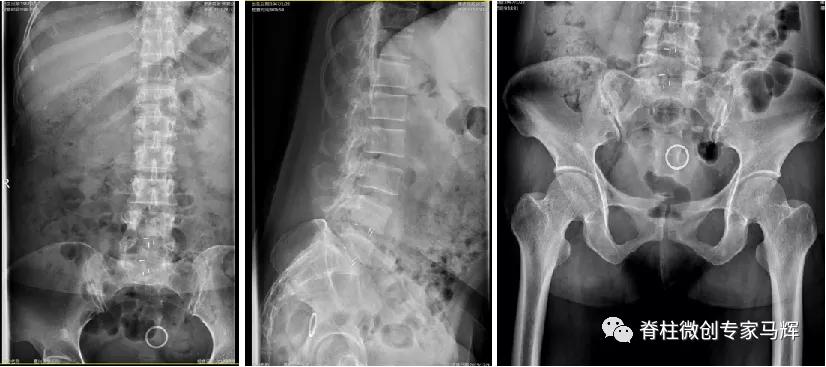

2019年腰椎内固定取出后

54岁的张女性,因为左髋部疼痛,行走不便2天,在当地医院就诊。查CT显示腰椎骨质增生,L2-3、L3-4椎间盘膨出。L4-5、L5-S1椎间盘术后改变,部分椎板缺如。L5-S1硬膜囊及右侧神经根受压而显示不清。入院后予以抗感染、活血等相关对症治疗,症状无明显缓解,当地医院建议转上级医院进一步诊治。为此,张女士一家慕名来到了上海第九人民医院脊柱外科就诊。